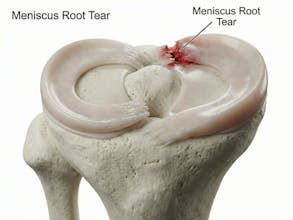

Natomy AI creates high-quality, medically accurate images and videos of human anatomy. Start with image-to-image: upload any low-quality photo, real image, or animation, and Natomy transforms it into an ultra-realistic anatomical visual. Unlike other AI tools that get anatomy wrong, Natomy is accurate every time—and fully editable by simply highlighting what you want changed and describing the update. Text-to-video launches in 2 weeks.